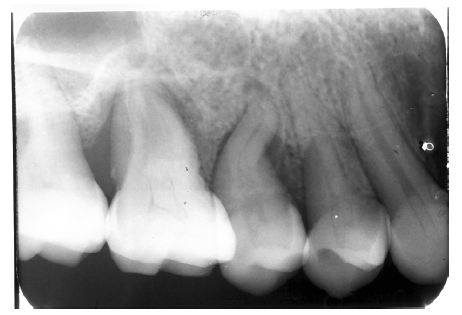

Dentin caries extends into the tooth dentin and can be recognized by noting the focal loss of dentinal radiopacity. Most commonly, this darkened dentin is located beneath carious enamel and, typically, the lateral dimension of the dentinal involvement exceeds that of the associated enamel caries (Figure 3). Dentin caries may be discerned interproximally, on the occlusal surface, buccally/lingually, or on root surfaces.

Figure 3 - Dentin Caries

Figure 3